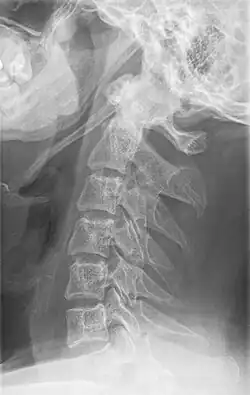

Radiograph, lateral view showing elongated stylohyoid process and stylohyoid ligament ossification -

Radiograph, lateral view showing joint-like formation in ossified stylohyoid ligament -

Imaging is important and is diagnostic. Visualizing the styloid process on a CT scan with 3D reconstruction is the suggested imaging technique.[13] The enlarged styloid may be visible on an orthopantogram or a lateral soft tissue X ray of the neck.